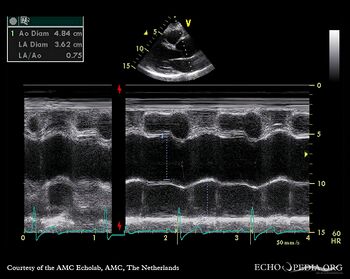

E00552.jpg

PLAX: dilated aortic root PLAX: 2-D measurement of aortic root

E00553.jpg

M-Mode through aortic root PLAX with Color Doppler: moderate aortic regurgitation